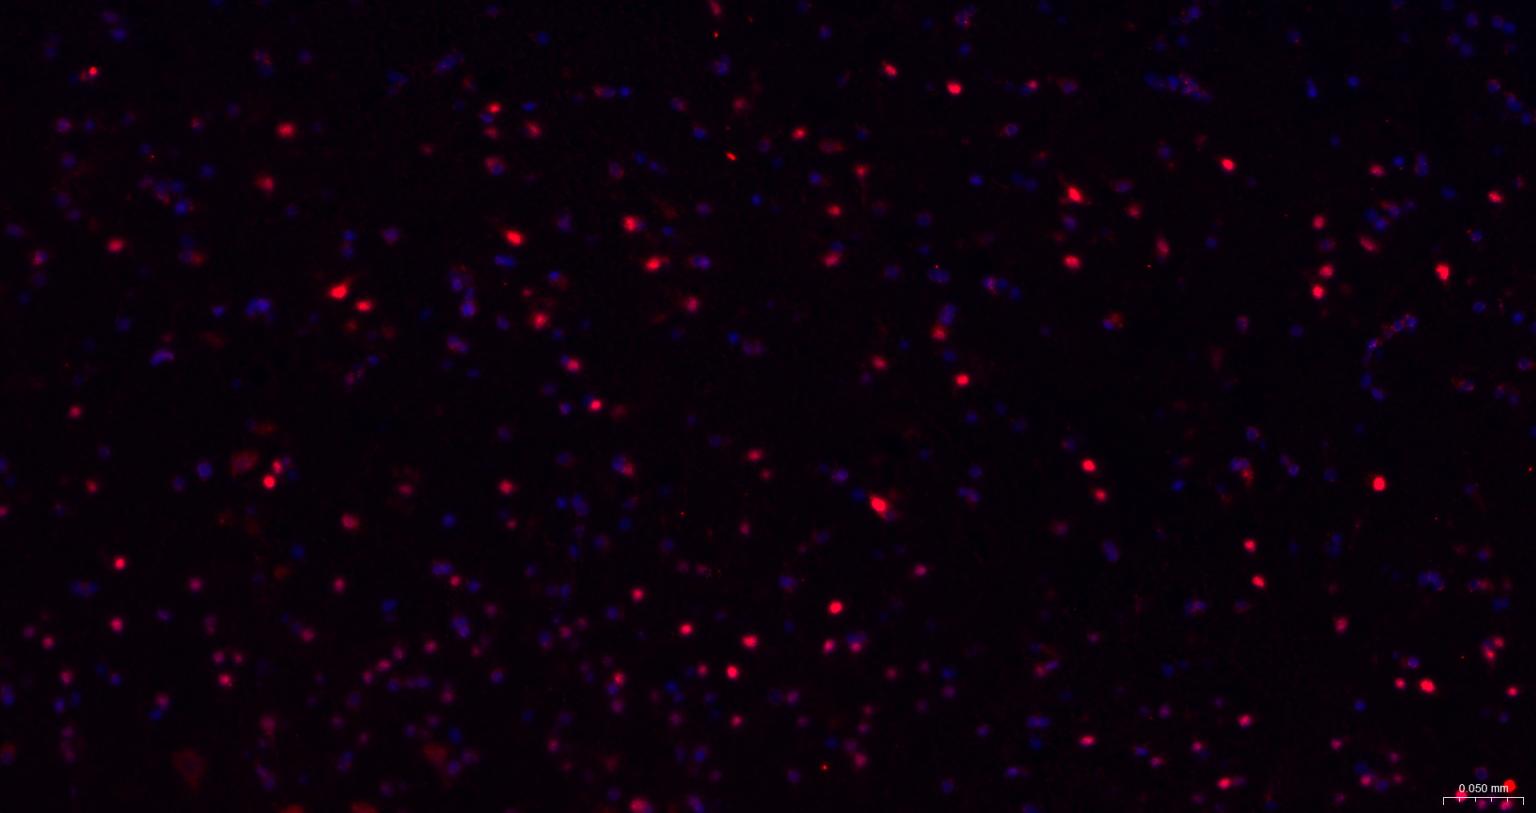

IHC-PHuman, Mouse, Rat1:100-500

IHC-FHuman, Mouse, Rat1:100-500

IFHuman, Mouse, Rat1:100-500